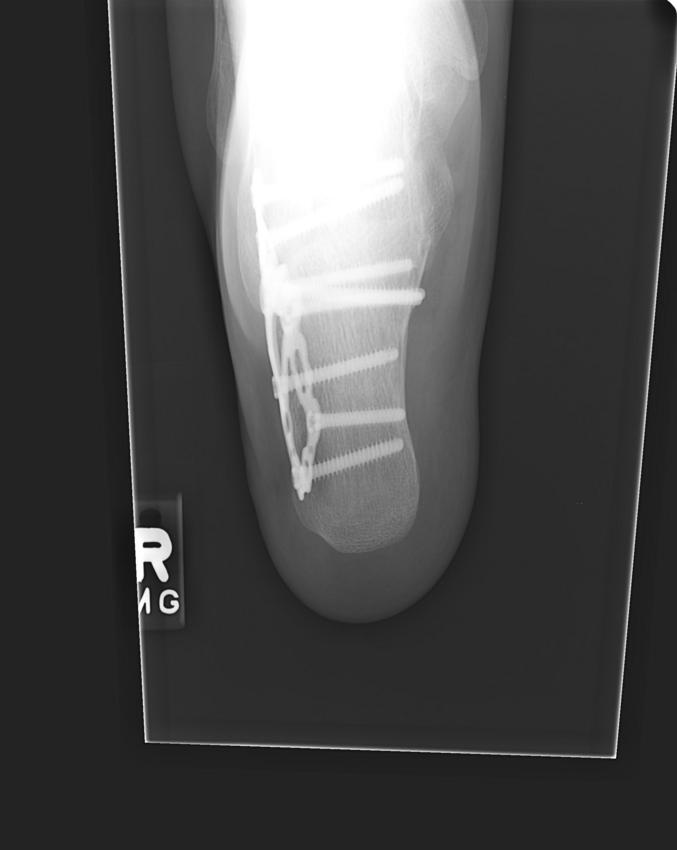

cracked heel

7 screws , steel plate